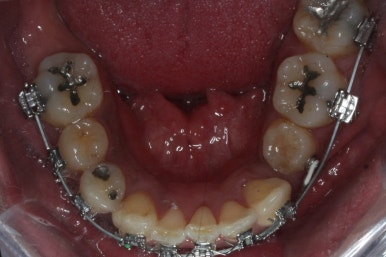

화살표 부분에 원래 송곳니가 있어야 되는데 보이질 않네요. 결손치아일 수도 있고 매복치아일 수도 있겠어요.

왼쪽 위 어금니도 한 개가 없어서 빈공간이 약간 남아있어요.

왼쪽 아래 작은 어금니는 아래쪽으로 많이 꺼져있네요.

이런 경우 X-ray 도 면밀히 관찰해 줘야 합니다.